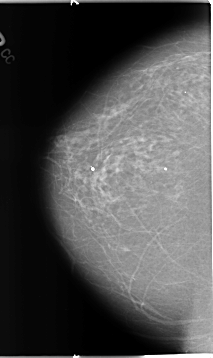

Digital Database for Screening Mammography

Volume: benign_01 Case: B-3126-1

B_3126_1.RIGHT_CC

RIGHT_CC LINES 4648 PIXELS_PER_LINE 2760 BITS_PER_PIXEL 12 RESOLUTION 50 NON_OVERLAY